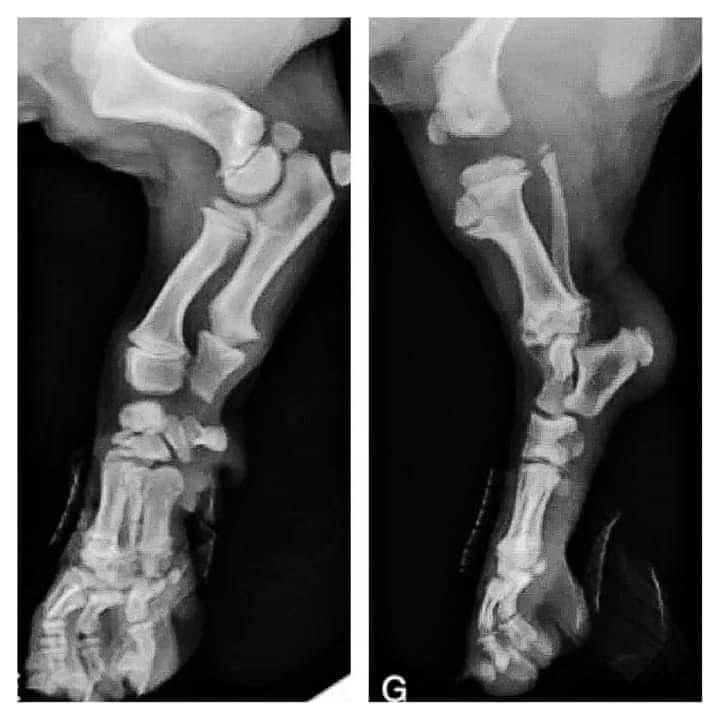

Hay que prestar especial atención al impacto durante el ejercicio en las placas de crecimiento del cachorro (para todas las razas)

Los huesos de los cachorros están rodeados de capas de tejido cartilaginoso suave que está en desarrollo y que se encuentra hacia el final de la mayoría de huesos largos.

Estas áreas de cartílago blando se conocen como placas de crecimiento.

Los huesos deben experimentar un crecimiento uniforme y si propiciamos una lesión en las placas con ejercicio físico intenso , con saltos sobre las patas traseras, etc…, vamos a detener ese desarrollo correcto y vamos a provocar un crecimiento irregular .

Si se produce una lesión en la placa de crecimiento, el avance del mismo con las células dañadas puede disminuir y detenerse, lo que significa que ya no habrá un desarrollo adecuado en la zona.

Cuando el crecimiento del lado afectado se retrasa o se detiene, el lado sano puede continuar creciendo y esa irregularidad puede llevar a una deformidad potencial.

Los cachorros son particularmente propensos a lesionarse durante el ejercicio vigoroso.

Cuando se cierran las placas de crecimiento ? Dependerá de la raza, las más pequeñas antes, las medianas sobre los 12 meses y las más gigantes hasta los 20 meses aproximadamente.

Otro factor a tener en cuenta son los efectos de las hormonas, si castras o esterilizas a tu perr@ antes de la pubertad, o sea desde los 4 hasta los 12/24 meses dependiendo de la raza, hay un retraso en el proceso de cierre de las placas de crecimiento, así mismo estos animales serán más propensos a desarrollar displasia de cadera, rotura de ligamentos cruzados e incluso cancer de huesos.